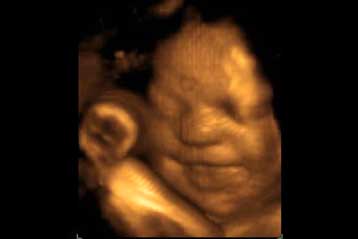

Τα μωρά που εκτίθενται σε επίπεδα τεστοστερόνης κατά τη διάρκεια της κύησης αντιμετωπίζουν μεγαλύτερη πιθανότητα να εκδηλώσουν συμπτώματα αυτισμού στην παιδική ηλικία, δείχνει έρευνα του Πανεπιστημίου του Κέμπριτζ.